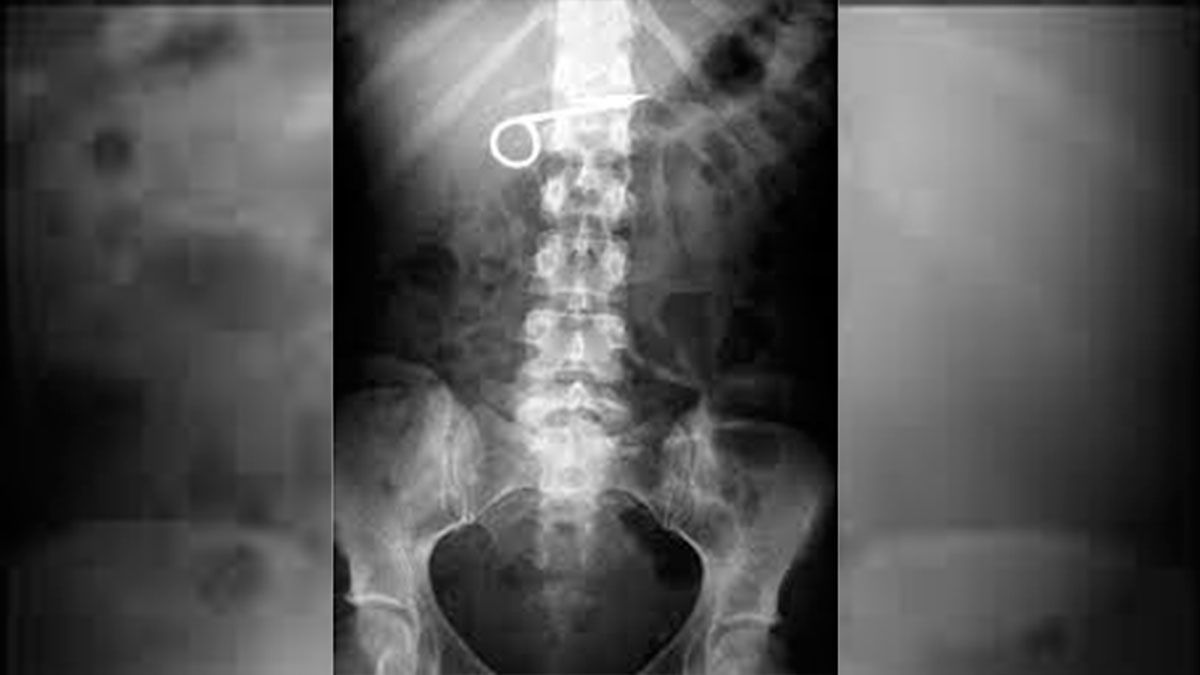

Allí fue atendido por el médico de guardia, quien tras solicitar una placa radiográfica, pudo constatar la presencia de objetos extraños dentro del cuerpo del reo, siendo estas: dos tijeras, un cepillo de dientes y el cabo de una cuchara.